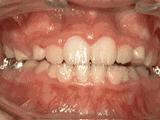

2、牙列不齐,牙齿异位,咬合关系紊乱,影响正常发音和正常咀嚼,经过矫正后是变成这样的~

3、牙齿拥挤,个别牙异位,牙弓狭窄,导致局部牙齿重叠生长,两侧各拔牙一颗后,经过矫正是变成这样的~

4、牙列拥挤,前牙没有咬合,上下牙齿中线不对称,牙弓狭窄,上颌“*牙虎**”异位生长,经专业评估没有拔牙,经过矫正后的牙齿是这样的~

5、开合,上下牙齿没有接触没有咬合,前牙没有咬合功能,无法咬切食物,会影响发音,经过矫正后的牙齿是这样的~

6、深覆合,咬牙时上牙全部覆盖下牙或覆盖过多;常出现,面容下三分之一过短,微笑时上颌露出牙龈过多,影响美观,经过矫正的牙齿是这样的~

8、前牙反合,俗称“地包天”,也就是咬牙时,下牙盖住上牙,正常情况应该是上牙盖住下牙,经过矫正后的牙齿可以变成这样的~